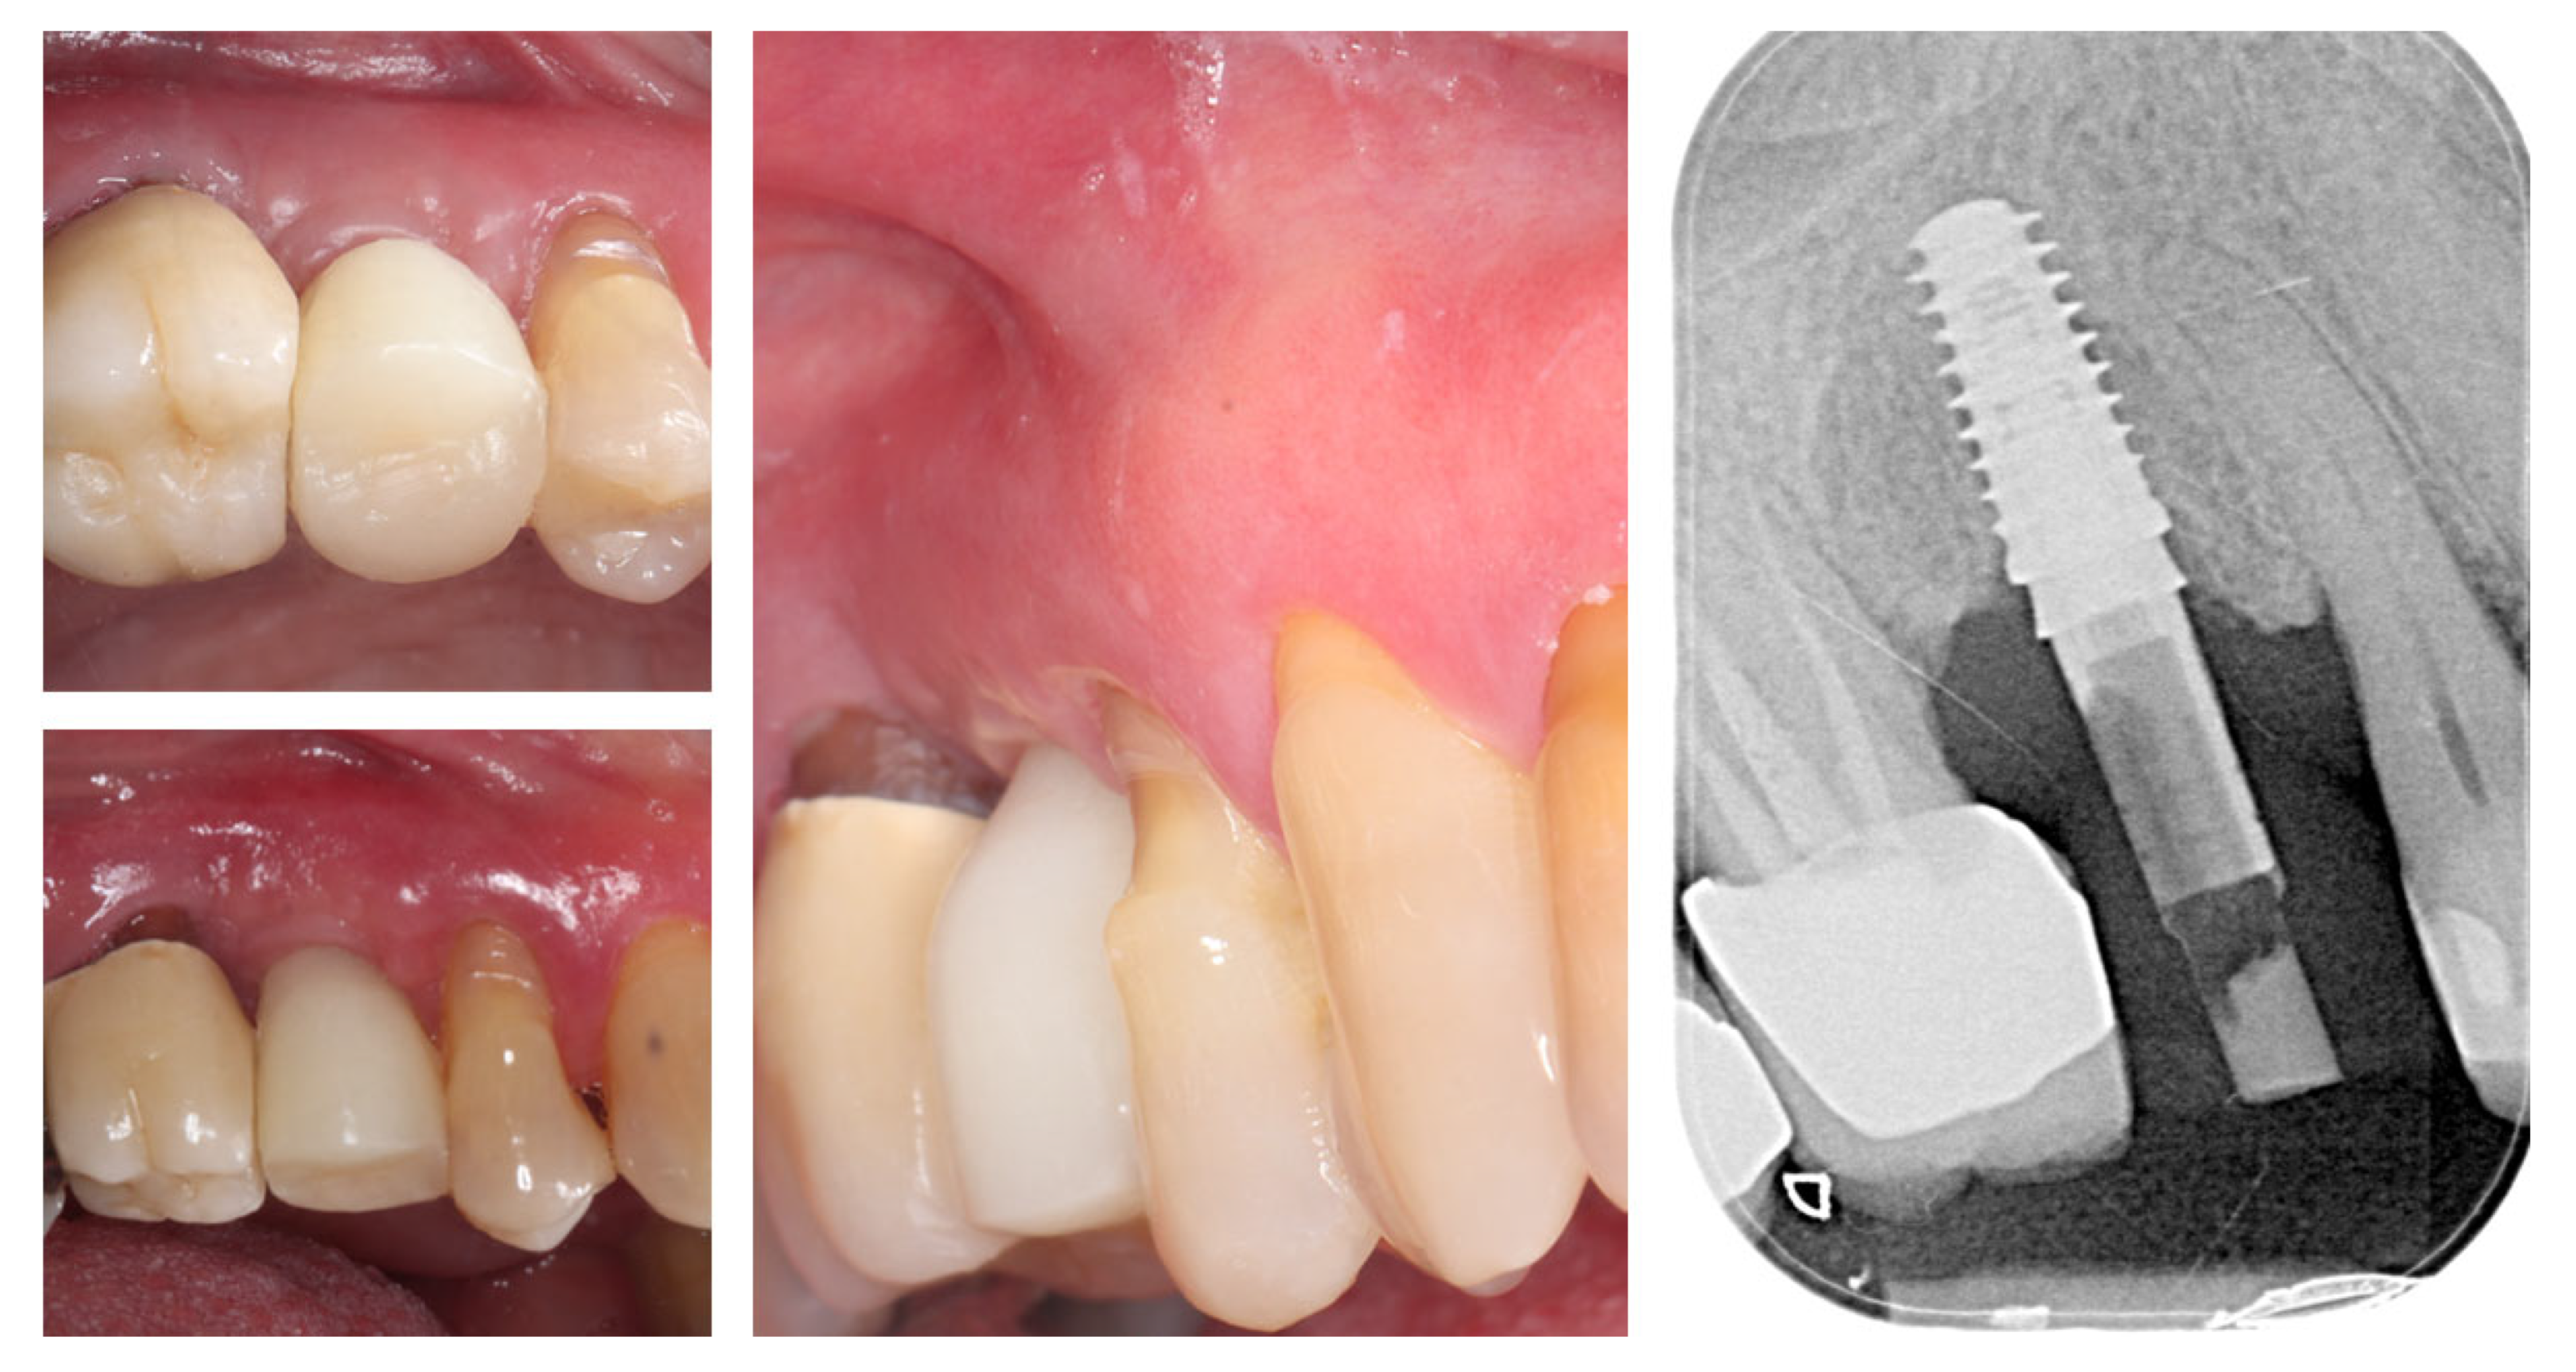

Digital volumetric analysis illustrates the stable increase in the peri-implant soft tissues over time, presented in (Figure 21). The buccal soft tissue dimensions increased from 2.3 mm horizontal thickness and 2.4 mm vertical thickness at baseline (Day 0) to 3.4 mm horizontal thickness and 3.4 mm vertical thickness at the 3rd month, showing approximately 1 mm thickness increase from the soft tissue augmentation procedure. One month after the connection of the temporary crown, the vertical thickness increased to 3.6 mm. At the time of the final crown placement, the horizontal thickness was 3.5 mm, and the vertical thickness was 4.10 mm, demonstrating the potential of the emergence profile of the crown to induce increase in the soft tissue thickness. The soft tissue thickness increase for the period of 8 months was 1.24 mm (53.45%) in horizontal dimension and 1.64 mm (66.67%) in vertical dimension.

Figure 21.

Digital volumetric analysis of the increase in the peri-implant soft tissues.

Figure 22 demonstrates the capabilities of the modern dental technology to assist the clinician in achieving accurate and reproducible results. The top row presents the congruence of the implant position with digital planning, while on the bottom row, the similarity between the prosthetic planning and the actual final crown is presented.

Figure 22.

Congruence of the implant position with digital planning and of the prosthetic planning with the final crown.

Table 1 summarizes horizontal and vertical soft-tissue thickness at baseline and during subsequent follow-up intervals (2 weeks, 3 months with provisional crown, 4 months post-provisional, 8 months with definitive crown, and 14 months post-definitive). Clinical and radiographic findings confirm uneventful healing, increased buccal thickness, stable mucosal margins, and preservation of crestal bone levels, supporting long-term soft-tissue stability.

Table 1.

Timeline of peri-implant soft tissue changes verified by digital analysis and clinical/radiographic follow-up.